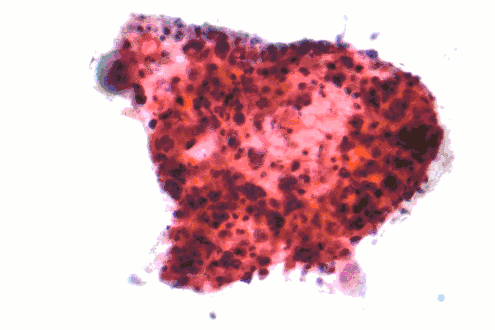

Squamous-cell carcinoma (SCC) of the lung is more common in men than in women. It is closely correlated with a history of tobacco smoking, more so than most other types of lung cancer. According to the Nurses' Health Study, the relative risk of SCC is around 5.5, both among those with a previous duration of smoking of 1 to 20 years, and those with 20 to 30 years, compared to "never smokers" (lifelong nonsmokers).[14] The relative risk increases to about 16 with a previous smoking duration of 30 to 40 years, and roughly 22 with more than 40 years.[14]

Micrograph of a squamous carcinoma, a type of nonsmall-cell lung carcinoma, FNA specimen, Pap stain. -